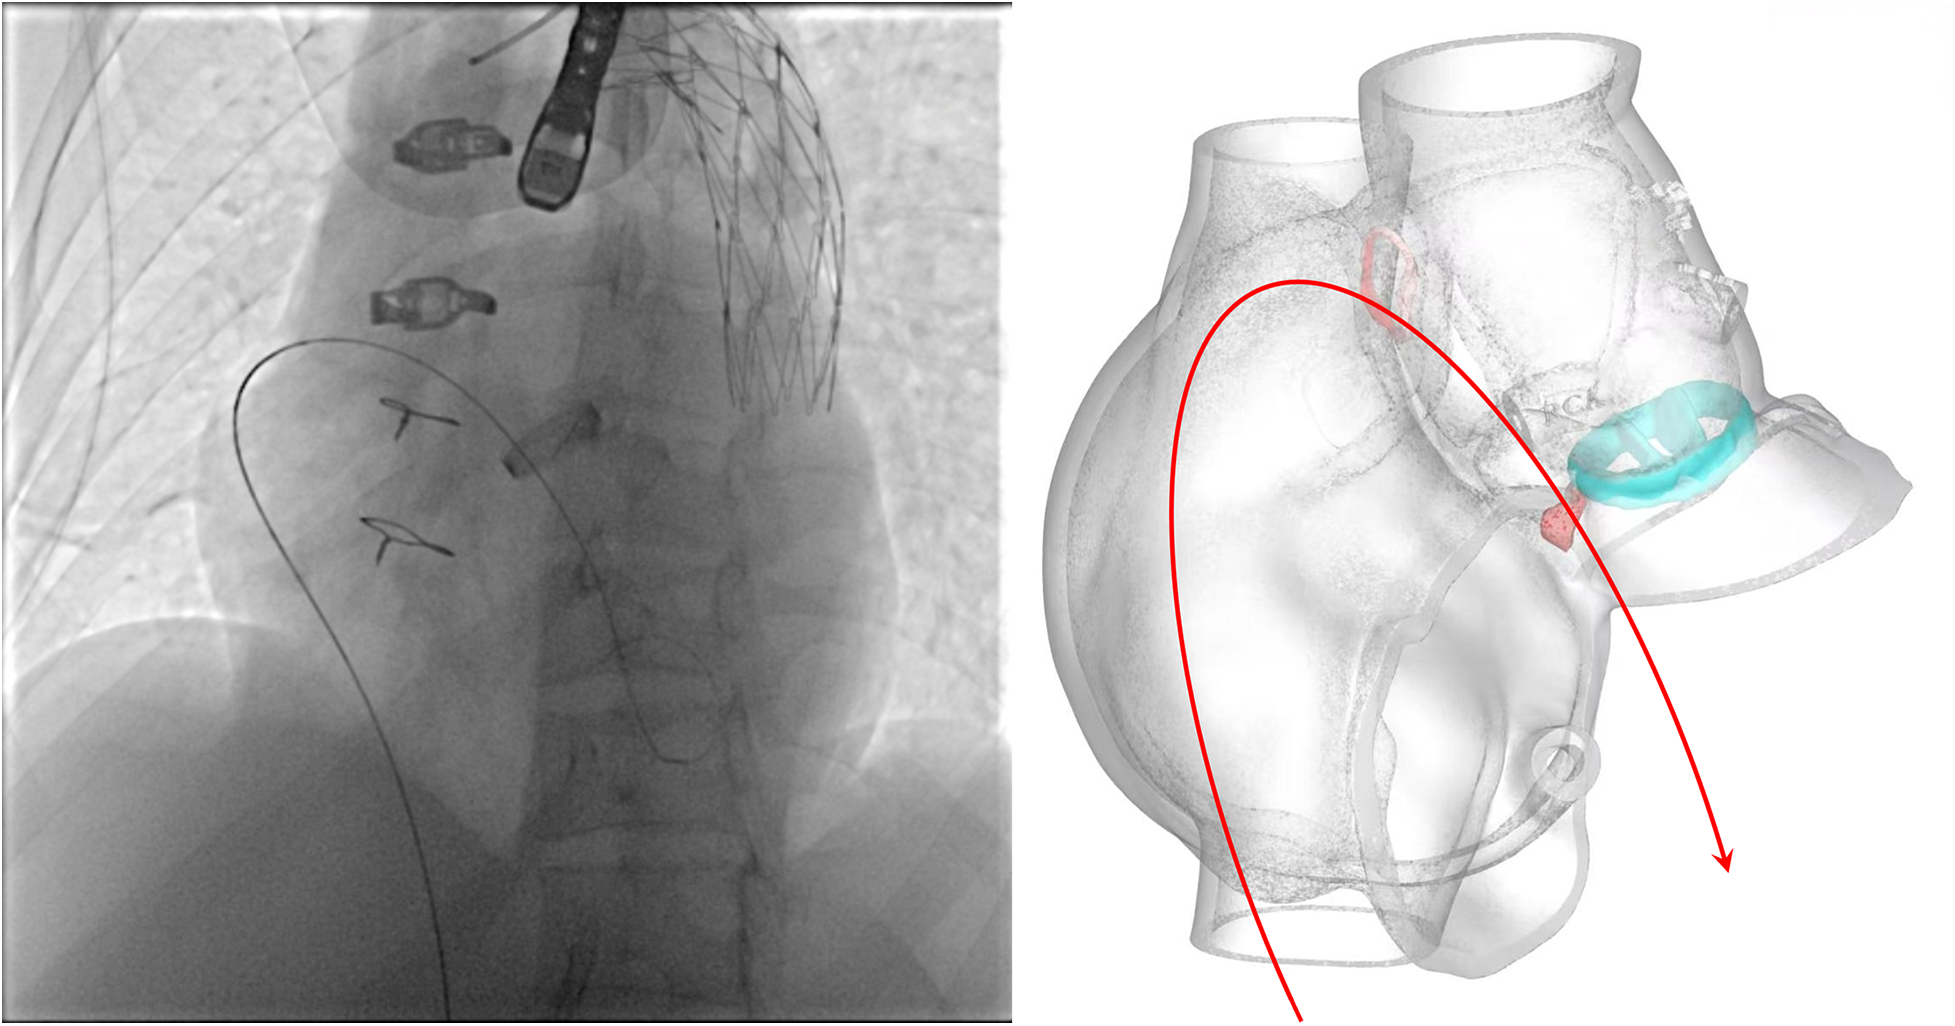

Unlike typical post-aortic valve replacement PVL, this case involved separation between the graft and native annulus (Figure 3), forming a pseudoaneurysm (A surgically-created autologous aortic adventitial chamber, communicating with the right atrium, serves to reduce surgical bleeding and is subsequently thrombosed for closure). The femoral arterial approach allowed only antegrade access to the defect. Left ventricular angiography was attempted to locate the leak, but it interfered with mechanical valve function, causing progressive bradycardia and hypotension, necessitating abandonment of the femoral approach. Subsequently, a right atrial approach was used to access the pseudoaneurysm via the Cabrol shunt from the initial surgery, followed by retrograde crossing into the left ventricle to establish a working pathway (Figure 4).

Figure 4

Schematic illustrating the pathway of the guidewire.

Initial attempt with a 6# VSD occluder (10 mm symmetric discs, 4 mm waist height, 6 mm waist diameter) failed due to device dislodgement. A 10# VSD occluder (14 mm symmetric discs, 4.5 mm waist height, 10 mm waist diameter) was then successfully deployed.